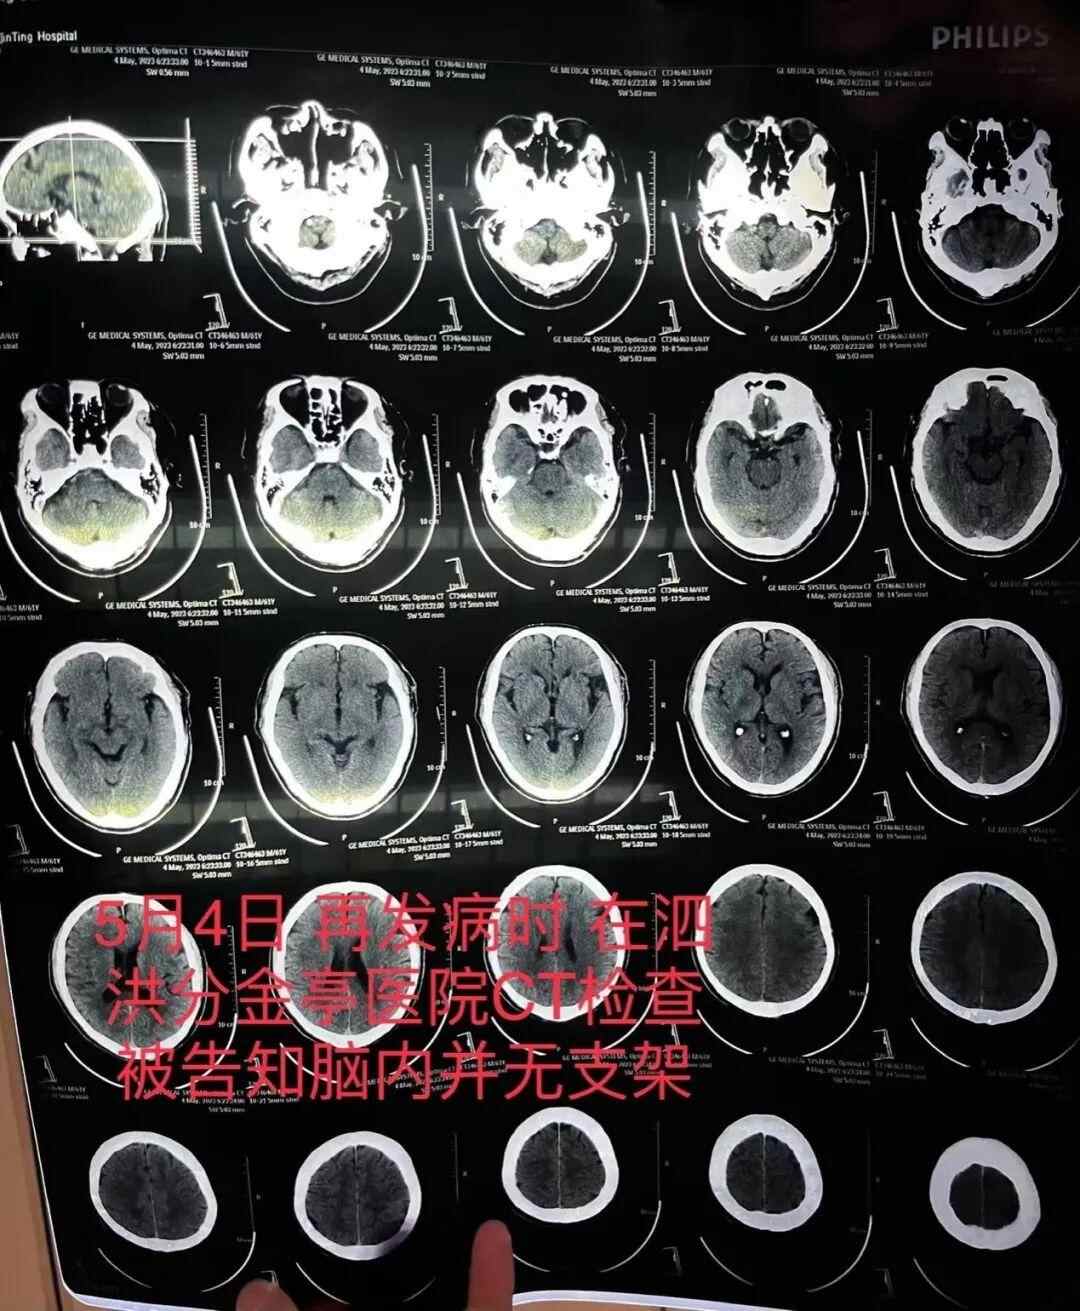

5月4日,朱老汉突发严重脑梗。他先被救护车送至江苏省宿迁市泗洪县分金亭医院抢救。令家属没想到的是,当时的CT检查发现,其颅内段部分动脉已严重堵闭,同时未发现此前植有支架。朱先生说,朱老汉又被转入宿迁第一人民医院,曾作为主刀医生的齐某此时才承认,之前未能在患者颅内血管成功植入支架。

朱老汉在泗洪县分金亭医院的CT检查报告显示颅内并无支架 朱先生供图